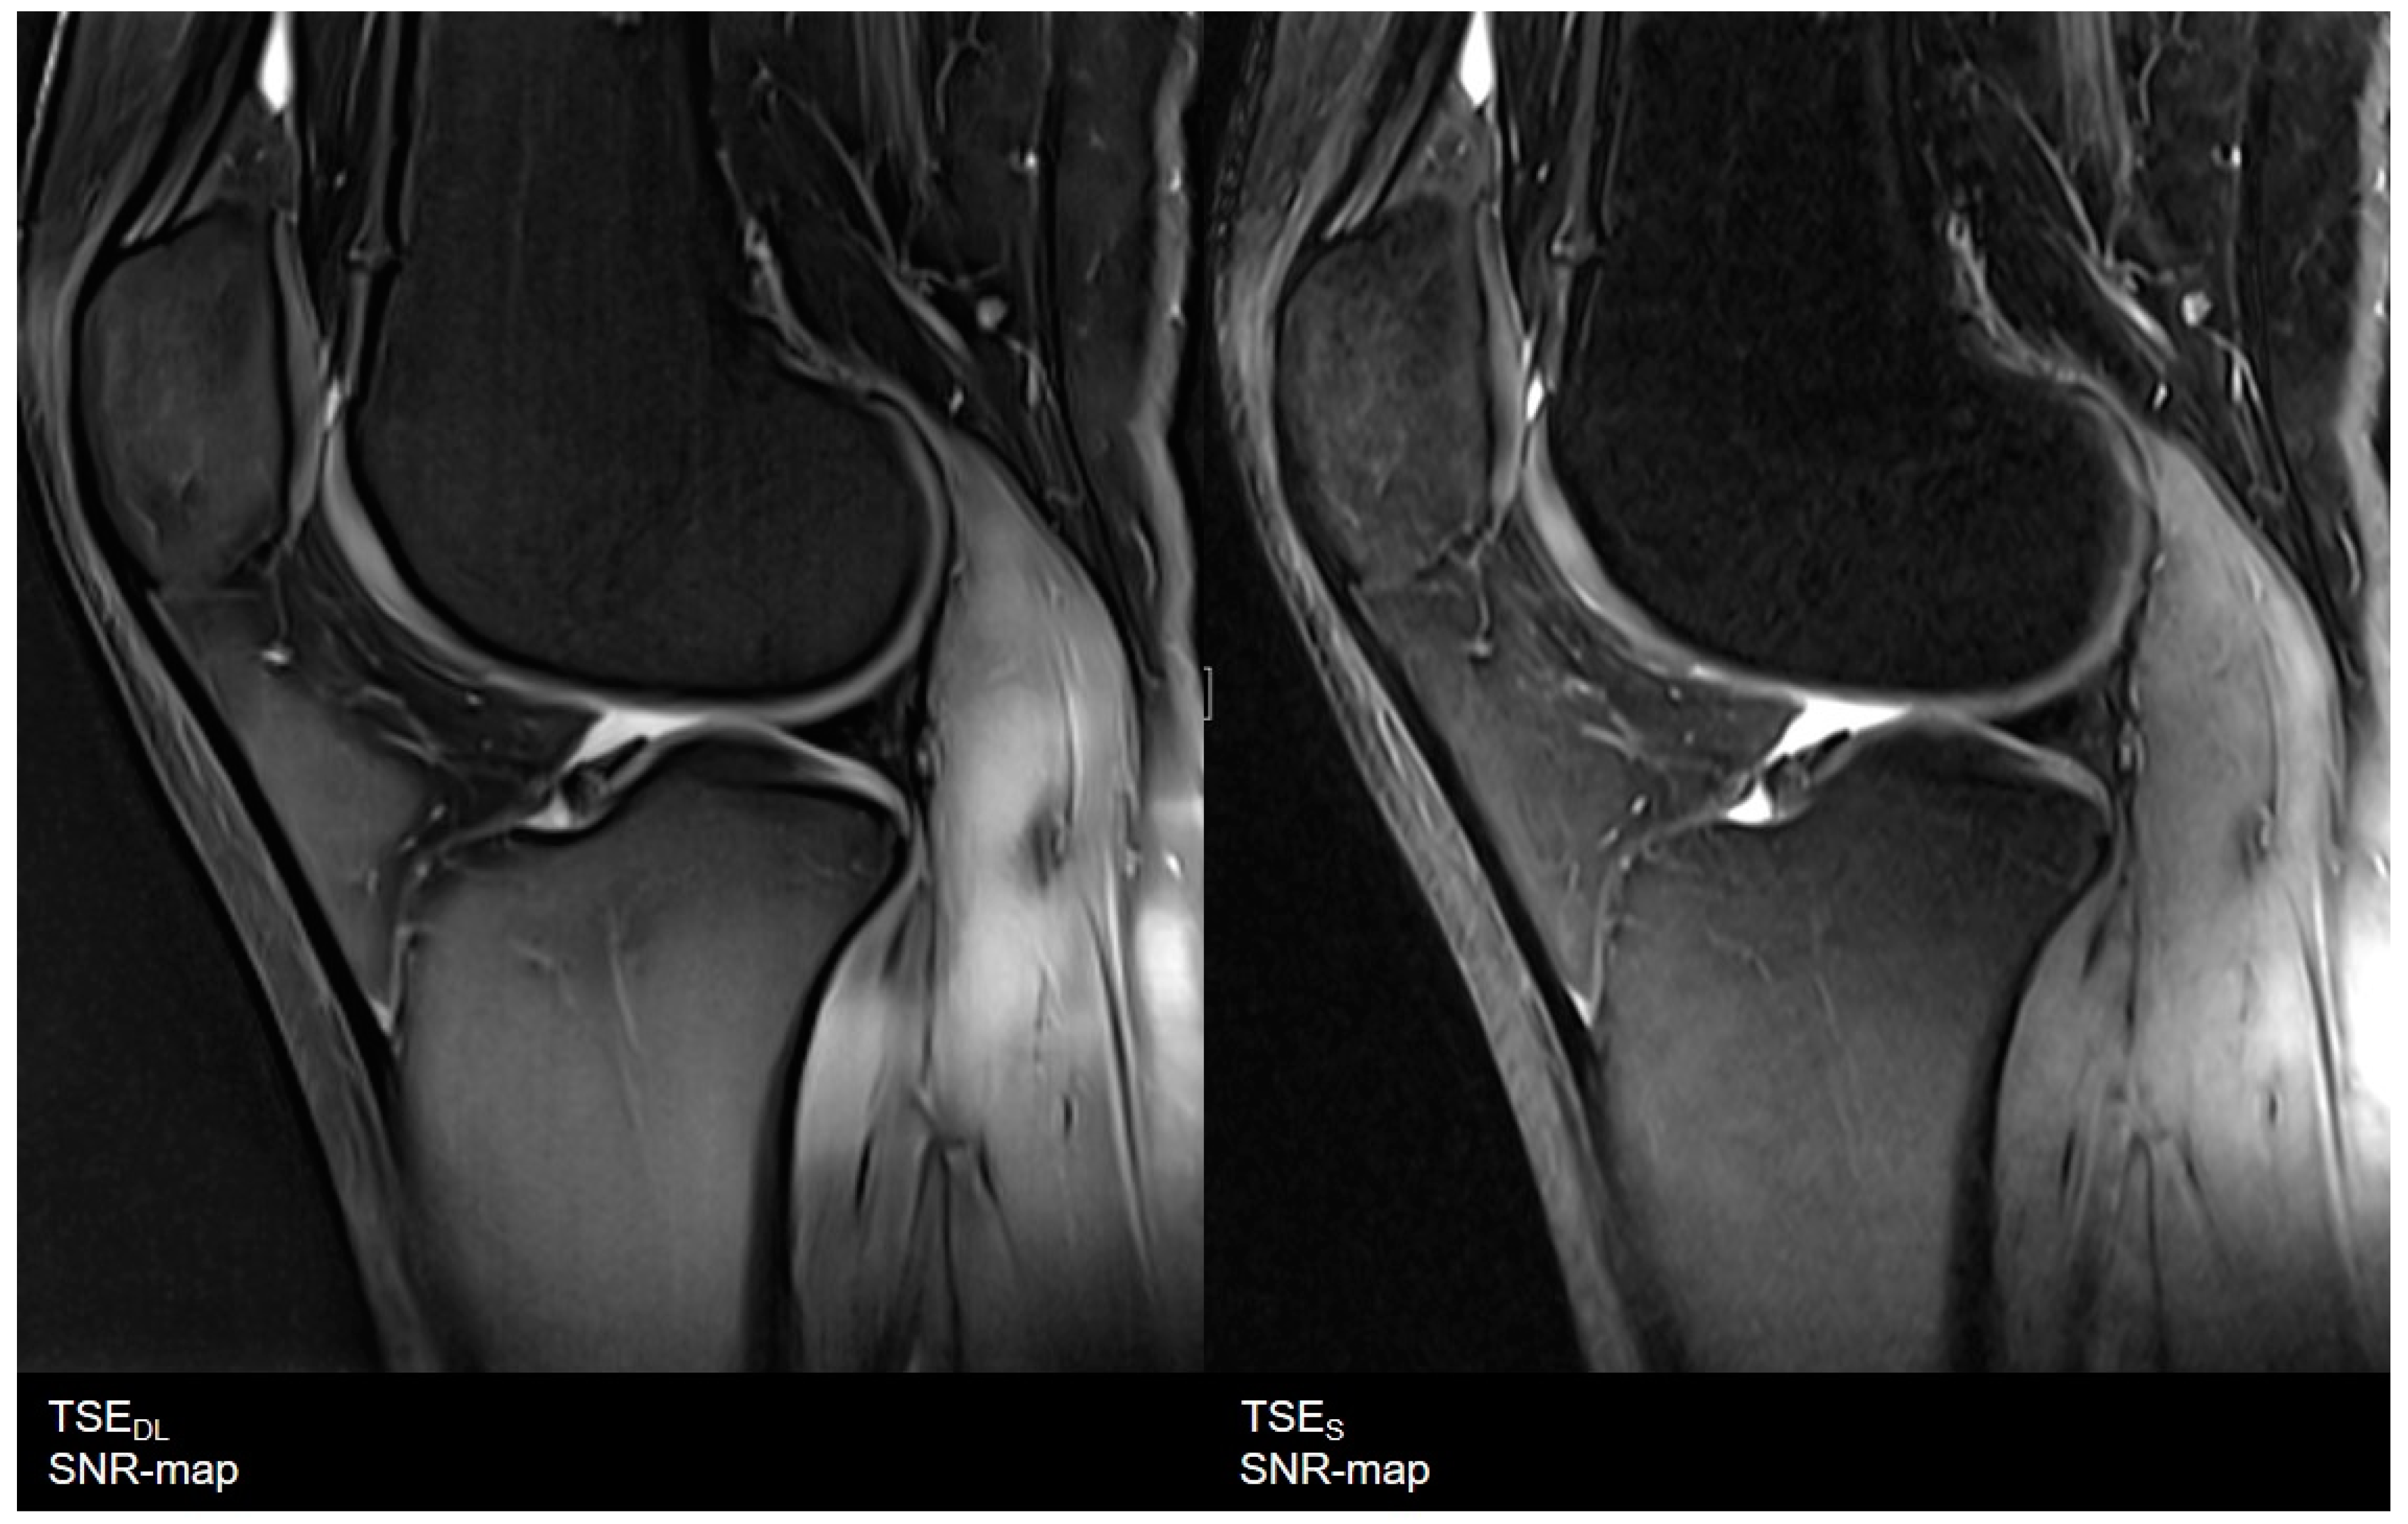

3.1. Assessment of Image Quality